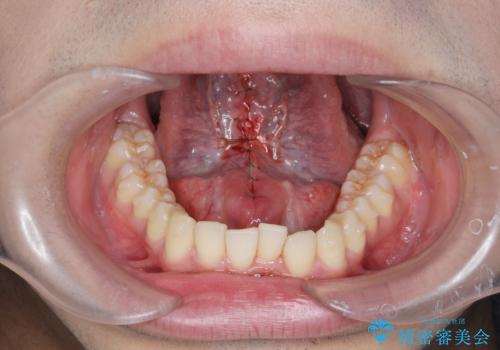

滑舌の改善 舌小帯の形成術

- 舌が動かしづらく、滑舌の改善を希望され来院されました。

舌小帯の形成術を即日で行い、1週間後に抜糸を行います。滑舌の改善を実感され、喜んでいただくことができました.

舌小帯の形成術は約10分程度で終了する小手術です。